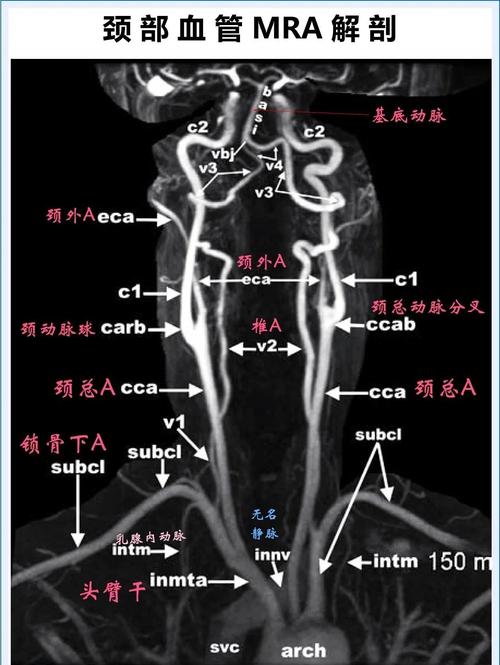

脑动脉狭窄是指供应大脑血液的动脉血管(如颈内动脉、大脑中动脉等)由于某些原因(如动脉粥样硬化、炎症等)导致血管内壁增厚、管腔变窄,血流通道变窄。

- 诊断方法:主要通过颈部血管超声、经颅多普勒超声、CT血管造影、磁共振血管造影或数字减影血管造影来确诊。